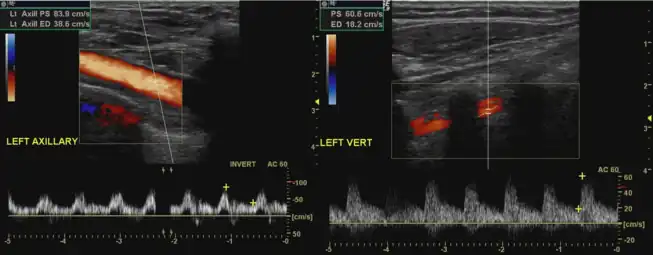

Doppler ultrasound of subclavian steal phenomenon